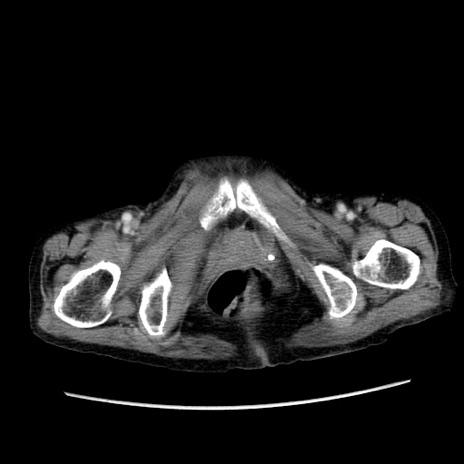

症例25(横断像)

【症例】80歳代女性

【主訴】胸のつかえ感

【現病歴】約9時間前に食後から胸のつかえた感じあり、嘔吐あり、来院。

【既往歴】胃癌(全摘)、胆摘、虫垂炎

【身体所見】心窩部に圧痛あり、反跳痛なし。

【データ】WBC 5700、CRP 0.05